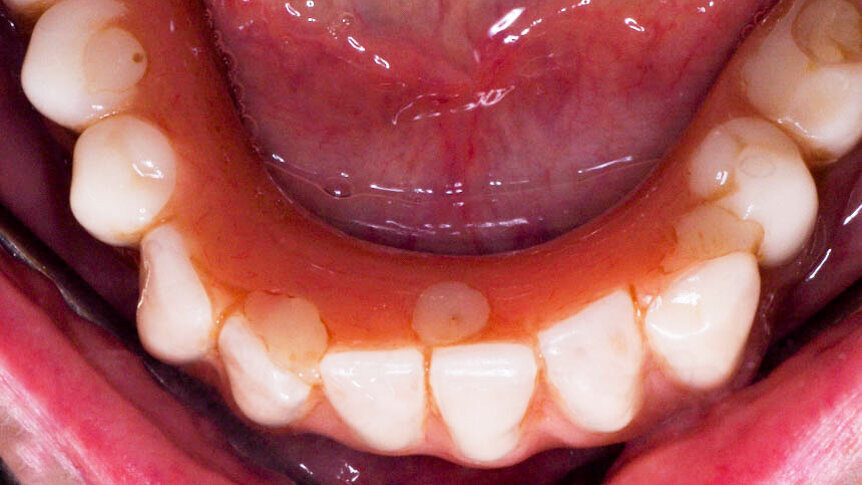

Figure 2a-c. Pre-operative clinical photographs.

Figure 4. Post-op intra-oral photo at 6 months after therapy

A 70-year-old female was referred for advanced peri-implantitis in the mandible. She presented complaining of pain and she also noticed discharge from one of the anterior implants. Her medical history was non-contributory and she was a non-smoker.

Clinical examination revealed 5 implants in the mandible supporting a fixed full arch reconstruction. Probing pocket depths were of the order of 8-9mm around 3 of the anterior implants. The distal implants had normal probing depths. CBCT imaging revealed an intrabony component of 6.1mm for the implant in the 43 position, 4.2mm at the 41 implant and 3.1 at the 33 implant.

Clinical parameters and radiographic examinations were performed at 3 and 6 months. At both intervals, there was resolution of the clinical parameters for all 3 implants, including plaque index, bleeding on probing and probing pocket depth. At these visits, non-surgical maintenance was carried out, including oral hygiene reinforcement and removal of biofilm via EMS AIR-FLOW® technology and EMS AIR-FLOW® PLUS Powder.